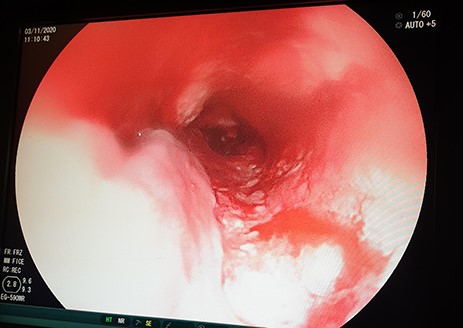

A 62-year-old male, a smoker and excessive alcohol consumer, non-hypertensive, presented with progressive grade-6 dysphagia that started gradually 7-month ago, associated with unintentional loss of weight. His biological brother was diagnosed with oesophageal cancer 3-year back and had an improvised GFT inserted but passed away shortly thereafter. On general examination he was weak, cachexic, severely pale, not jaundiced, not cyanosed with bilateral pitting lower limb edema with vitals within normal range. Full blood picture initially showed microcytic hypochromic anaemia of 6.4 g/dl, other parameters were essentially normal. Chest X-ray and abdominal ultrasound were essentially normal. Patient did an OGD which revealed at 20 cm a fungating mass partially obstructing lumen (Fig. 4), a biopsy was taken but the scope could not pass through. Histology results for biopsy showed oesophageal invasive squamous cell carcinoma grade 2.

OGD showing a fungating mass partially obstructing esophageal lumen.